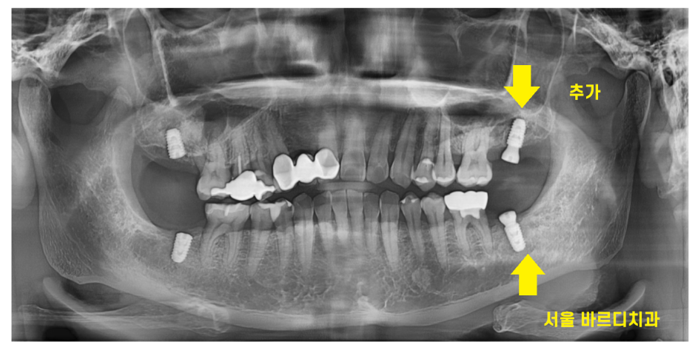

231125

한달 간격으로 오른쪽, 왼쪽 수술을 진행하여

완성은 동시에 끝내드렸습니다.

어금니 4개가 추가적으로 생기셨으니

맛있는 거 더 많이 드실 수 있겠습니다.

소화도 더 잘되실 것이고요